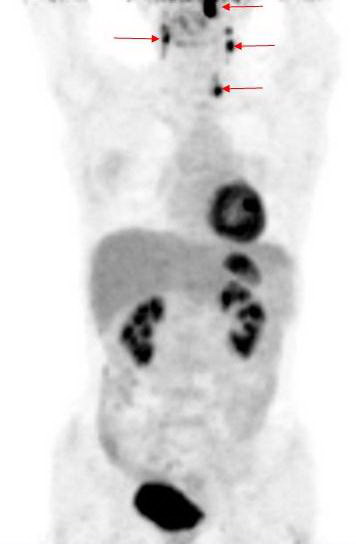

Hình 1: Hình ảnh PET tổng thể cho thấy các tổn thương tăng hấp thu FDG bất thường tại các vị trí mũi tên.

Kết quả PET/CT: tổn thương tăng hấp thu FDG mạnh tại vòm họng bên trái, max SUV=11,8, các tổn thương di căn hạch tại vùng cổ bên phải và bên trái.

Trong khi đó kết quả nội soi vòm họng và CT không phát hiện thấy tổn thương u nguyên phát (CT-) bởi vì tổn thương ở mức độ chưa xâm lấn ra bề mặt niêm mạc vòm họng và mà mắt chưa thể nhận thấy được  qua  nội soi, CT...

Dựa vào các kết quả trên, bệnh nhân được chẩn đoán là ung thư vòm họng di căn hạch cổ hai bên. Đồng thời đánh giá được giai đoạn bệnh của bệnh nhân là T1N2M0, kế hoạch điều trị tiếp theo là xạ trị phối hợp hoá trị.

Như vậy, ghi hình bằng máy PET/CT đã giúp ích rất nhiều trong việc chẩn đoán,  phát hiện tổn thương ung thư nguyên phát một cách chính xác, nhanh chóng, hiệu quả mà các xét nghiệm khác như CT, MRI… chưa phát hiện được.